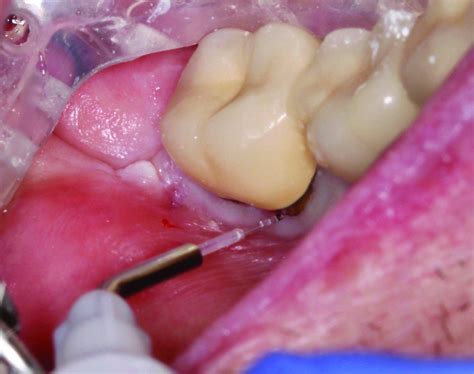

How Soft Tissue Diode Laser Works Without Needing Stitches